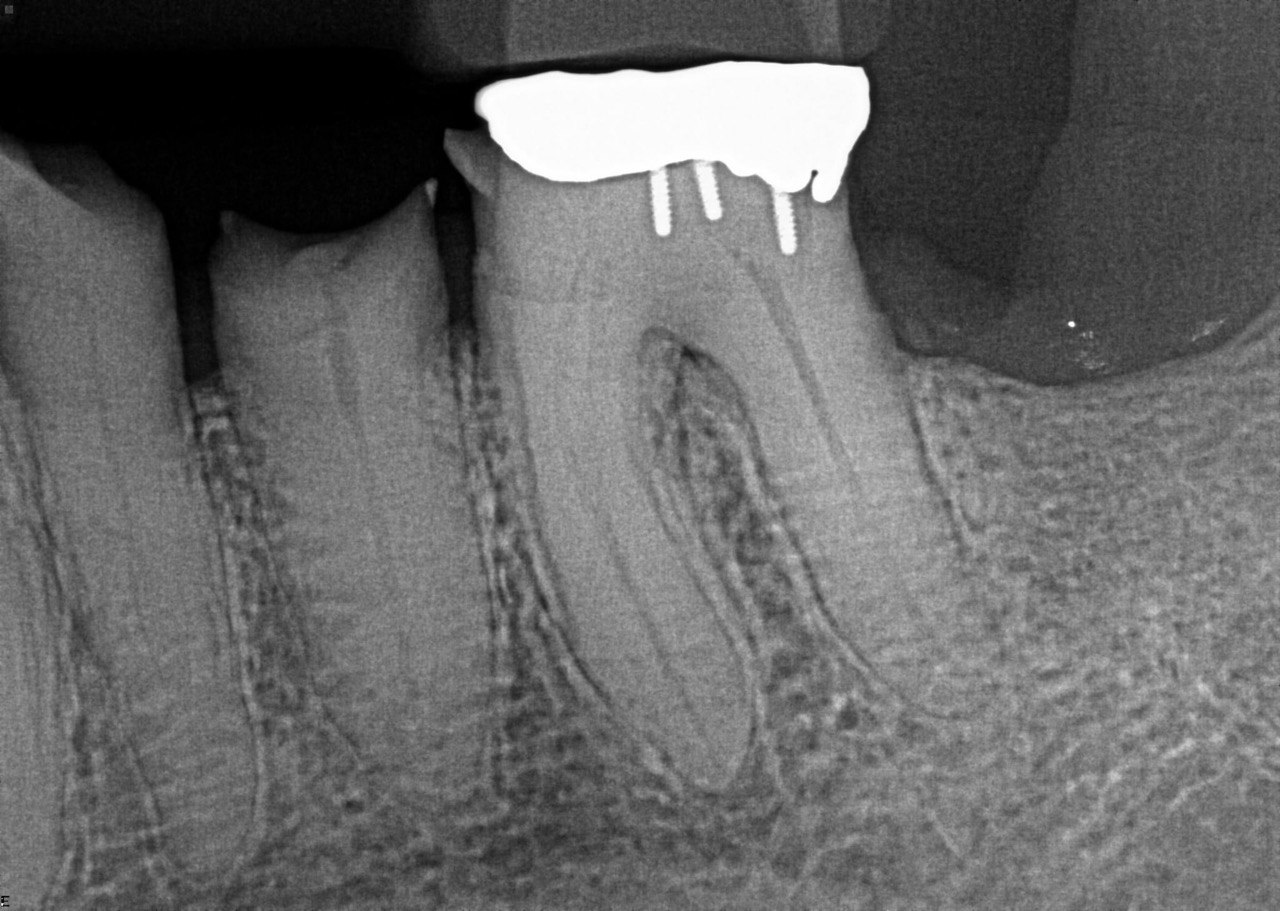

Question 3: Which option is not evident on the print of the X ray?